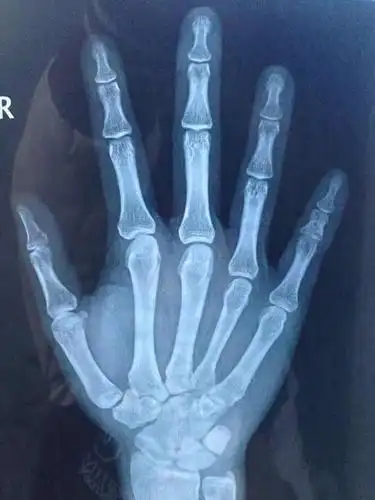

(这是6岁男孩的骨骺)

骨龄偏大一岁

今天去拍了手骨的片子看看骨骺线闭合没,还能长多高,懂的人给我看看吧

今天去医院检查了骨骺线和生长激素,医生说还没有完全闭合,但是我已经

如何确诊指骨骨骺早闭?